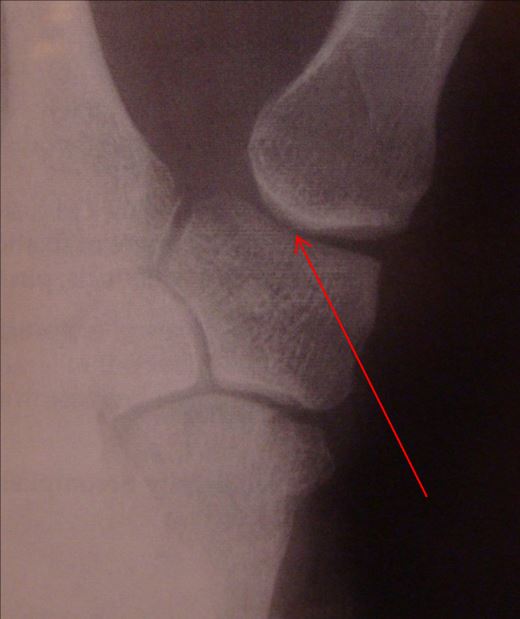

Xray of patients' left hand in three planes showing signs of basal Basal Joint Arthritis Golf There’s no need to hang up your golf. Can golfing and arthritis mix? Fortunately, there are a variety of things you can do — from choosing gear to exercises to changing grip — to keep on playing golf without extra pain. As a golfer with the condition, you’re likely to experience stiffness in your arthritic joints, reduced range of motion,. Basal Joint Arthritis Golf.